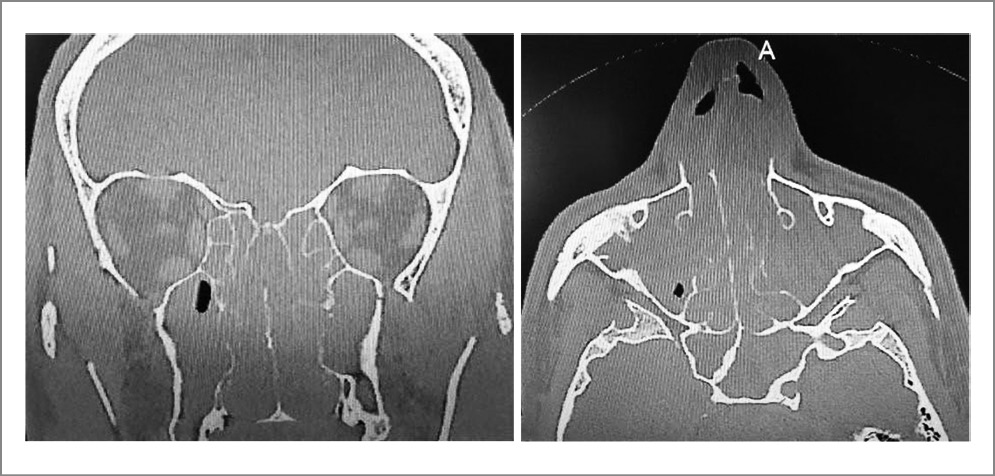

Учитывая клинические признаки, пациенту проведена компьютерная томография околоносовых пазух. Выявлены мягкотканные структуры, практически полностью заполняющие полость носа и околоносовых пазух, плотностью 40–45 едH с частичной деструкцией медиальных стенок верхнечелюстных пазух (рис. 1).

Рис. 1. Компьютерная томография околоносовых пазух. РЭАГ и полипоз полости носа и околоносовых пазух.